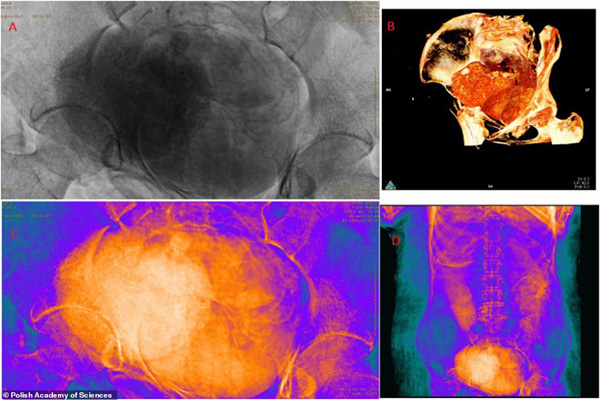

این تیم با استفاده از ترکیبی از سی تی اسکن و اشعه ایکس ، بقایای جنین حدود 26 تا 30 هفتگی را در داخل بدن این زن مومیایی کشف کرد و به این ترتیب نخستین مومیایی باردار جهان شناسایی شد.